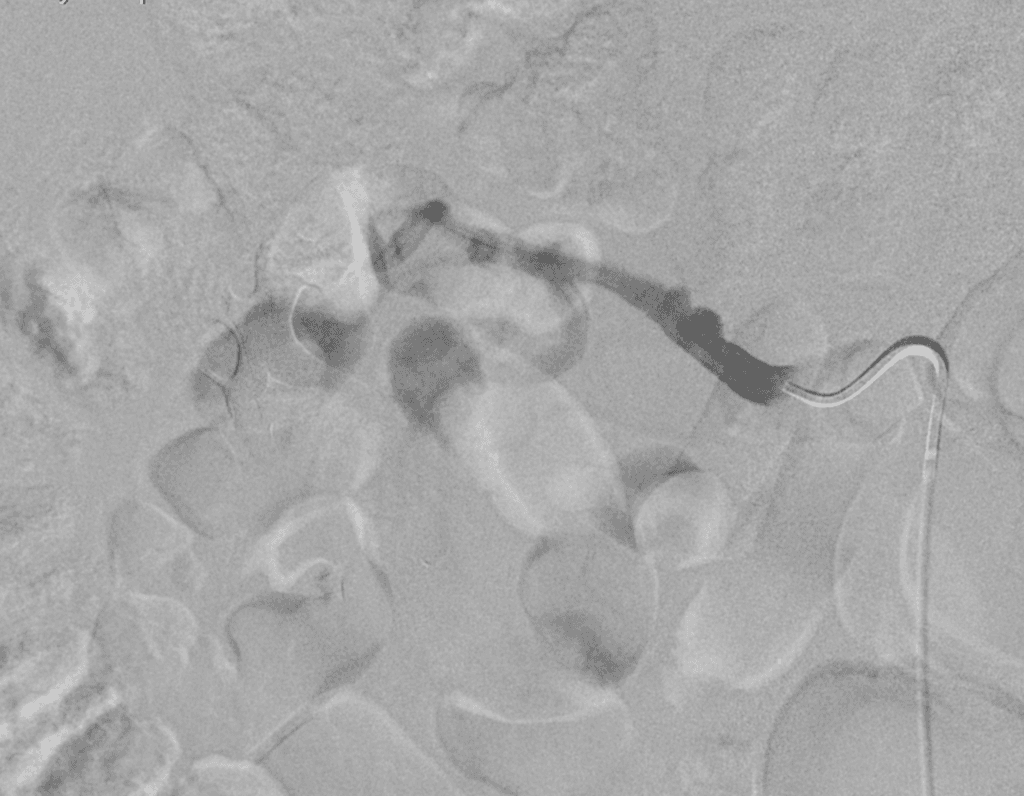

- Khi tiêm thuốc cản quang, thấy một đoạn hẹp nặng dài ở vùng trực tràng-xích ma, dài khoảng 9 cm.

- Thuốc cản quang đi qua đoạn hẹp ở phía gần và làm đầy lòng đại tràng.

- Ngoài ra, thấy rõ hình ảnh rò trực tràng - âm đạo (rectovaginal fistula), thuốc cản quang đi vào ống âm đạo.

- Phát hiện rò trực tràng - âm đạo (rectovaginal fistula) và hẹp đoạn dài ở trực tràng-xích ma (long-segment rectosigmoid stricture), còn gọi là dấu hiệu dây (string sign), ở bệnh nhân mắc bệnh Crohn (Crohn disease) đã lâu.

Bệnh Crohn (Crohn disease) với dấu hiệu dây (string sign) và rò trực tràng - âm đạo (rectovaginal fistula)